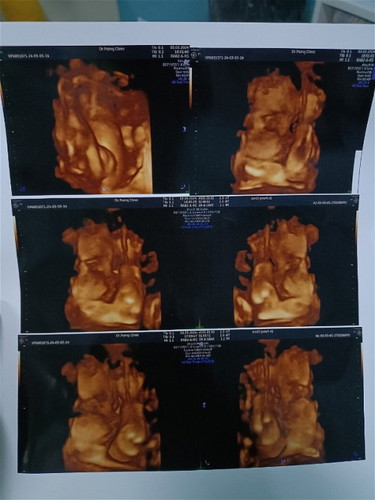

ท้องที่ 3 กำหนดคลอด23/5/67 นี้ อายุครรภ์ 28+5 วีค น้ำหนักน้อง1,200+ กรัม ถือว่าใหญ่ไหมคะ แม่อายุ 26 ปี สูง 168 นน. 53.5 ถือว่าตัวเล็กมากๆ แพ้หนักมากตอนท้องนี้จากเดิมหนัก 54 แพ้ท้องตั้งแต่เดือนแรกถึง4-5เดือน นน.ลงไปเหลือ 49.9 ตอนนี้เพิ่งขึ้นมา 53.5 ค่ะ

Baby 3 ♥️